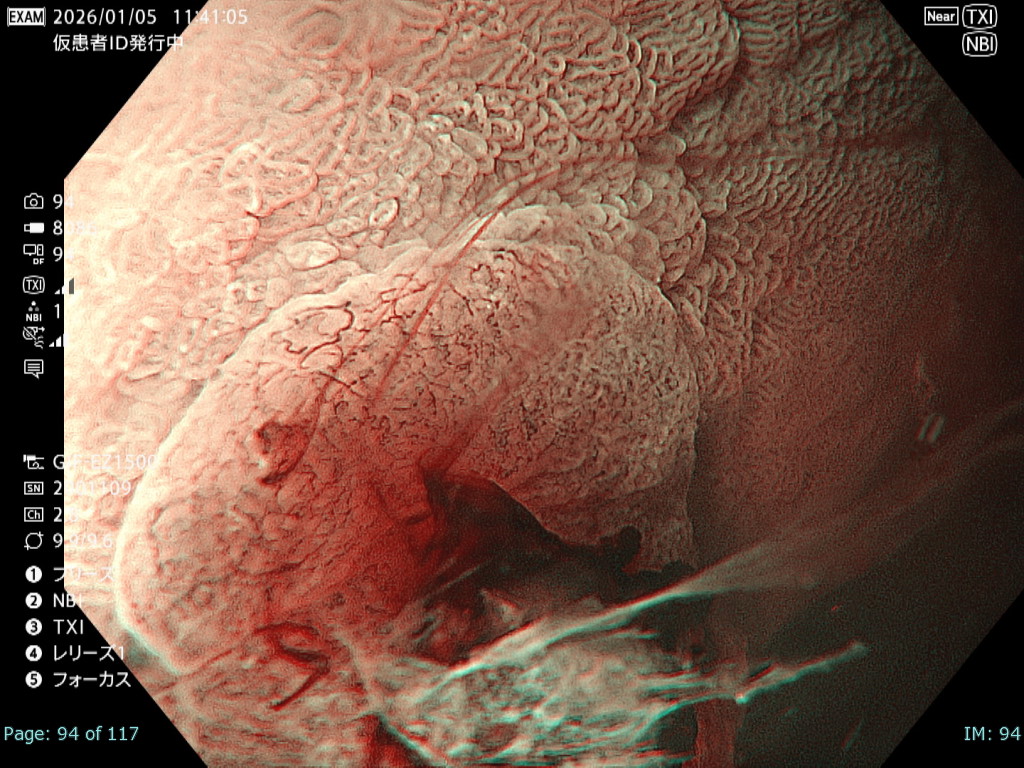

• NBI観察②(拡大)

強調設定:B8

図5

病変は易出血性で観察難易度が高く、NBI拡大観察では微小血管構築像は視認可能であるものの、出血の影響で一部で輪郭が不鮮明となった。

• NBI+TXI観察② (拡大)

切替前 NBI強調設定:B8

NBI+TXIレベル:中

図6

出血の影響を受ける条件下でも、NBI+TXI拡大観察は、NBI拡大観察と比較し、微小血管構築像がより明瞭になる印象だった。